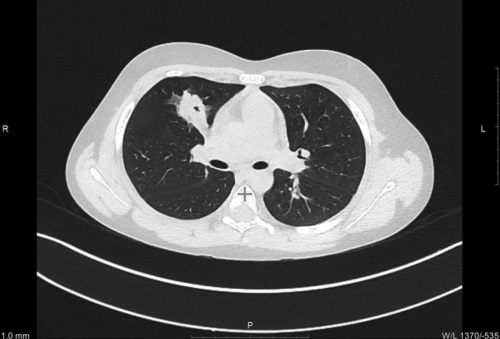

Введение. Рак легкого у детей — крайне редкая патология, встречающаяся менее чем в 0,2 % случаев всех детских опухолей. Наиболее часто выявляются аденокарцинома и карциноидные опухоли, которые, как показывают последние мультицентровые исследования, нередко диагностируются уже на поздних стадиях из-за отсутствия специфической симптоматики и трудностей дифференциальной диагностики. Материалы и методы. В статье представлен клинический случай инвазивной муцинозной аденокарциномы легкого у ребенка 9 лет. Результаты. Опухоль выявлена случайно при выполнении компьютерной томографии грудной клетки. Изменения в легких были расценены как деструктивная пневмония, по поводу которой пациент длительно получал лечение, на фоне которого наступило клиническое улучшение. Однако при контрольной компьютерной томографии была выявлена отрицательная динамика. Учитывая локализацию изменений в одной доле, после проведенной предоперационной подготовки пациенту была выполнена верхняя лобэктомия с систематической медиастинальной лимфодиссекцией. Гистологически установлен диагноз: инвазивная муцинозная аденокарцинома легкого. Специальное противоопухолевое лечение не проводилось. Пациент находится под динамическим наблюдением без признаков рецидива. Обсуждение. Данный клинический случай показывает проблемы диагностики рака легкого у детей, а также проблемы стадирования заболевания и определения тактики лечения. Заключение. Подчеркивается необходимость разработки четких клинических рекомендаций по диагностике и лечению рака легкого у детей с учетом анатомо-физиологических особенностей детского организма.